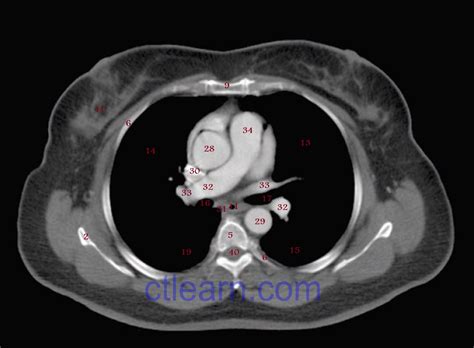

A CT of thorax, or computed tomography scan of the chest, uses X-rays and computer technology to create cross-sectional images of the thoracic cavity. These images provide a detailed view of the lungs, heart, blood vessels, and other structures within the chest. The procedure is particularly useful for diagnosing conditions such as lung cancer, pneumonia, and heart disease.

Interpreting the results of a CT of thorax involves a radiologist reviewing the images to identify any abnormalities. The findings are then communicated to the referring physician, who will discuss them with the patient. Common conditions that can be detected include:

Radiologists use advanced software to analyze the images, providing detailed reports that guide further treatment and management.